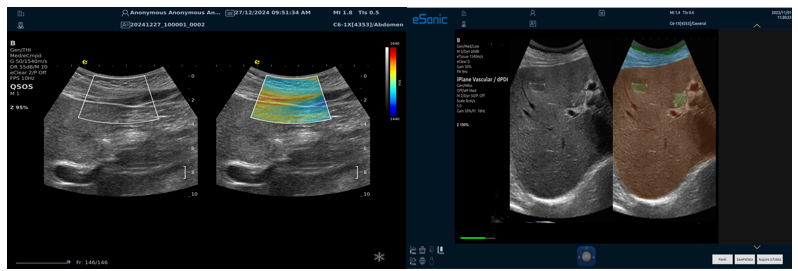

QSOS声速定量成像

测量原理

QSOS声速成像技术利用声波在组织中的传播速度差异性,计算不同位置的声速值,反映组织的物理特性。

成像过程

利用超声探头发射超声波脉冲,分析反射信号的时间延迟,确定声波传播路径和速度,构建声速分布图像。

图像显示

QSOS技术采用彩色编码显示声速图像,不同颜色代表不同声速值,便于医生识别病变部位和测量。

25fb8cb17586b86e5d915a2be3025a2.png

技术优势

?精准定量反映组织特性,成像更敏锐?彩色编码直观显示,轻松发现异常?捕捉声速差异,早期、微小病变更易察觉

肌骨22.png

肌骨领域的应用

?精准定位损伤部位?判断损伤严重程度?监测肌肉营养?评估肌少症?骨质疏松评估

08bce87534cf2cf9f10c1dfc5b314dd.png